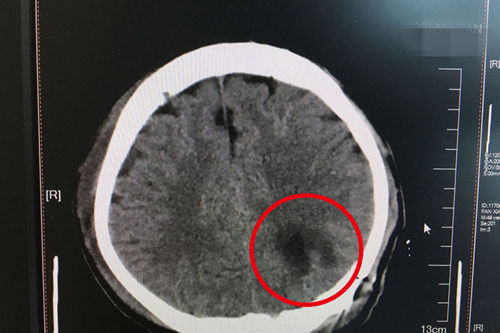

患者術(shù)后CT顯示:病灶已被完整清除,即右下角深色塊狀部分